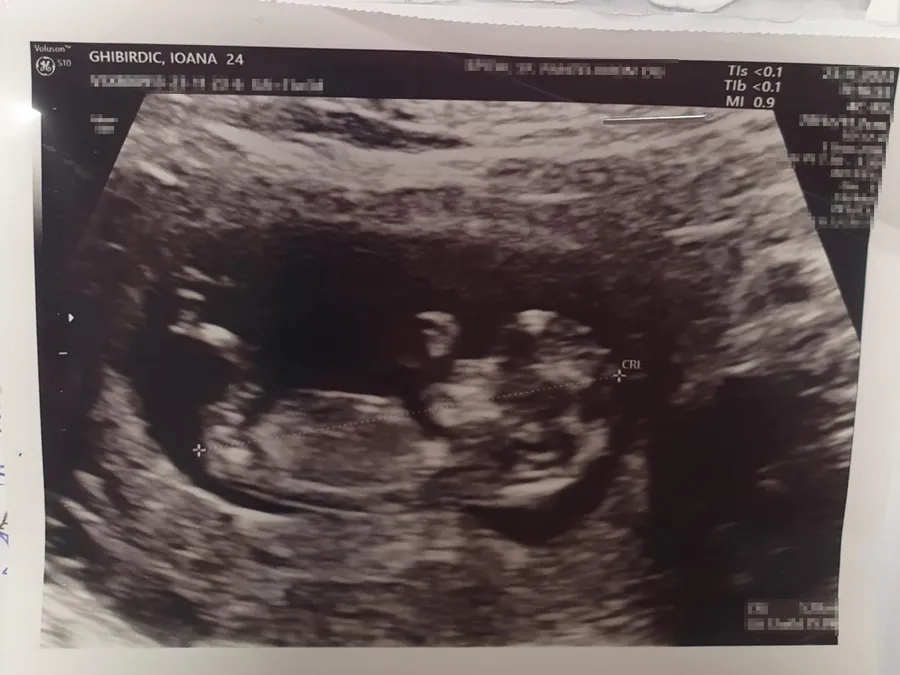

”Vor fi doi îngerași. Unul mai mare, fiind fata, pe care vom pune o fotografie și vom scrie ceva și unul mai micuț, fiind fetița, bebelușul, pe care o sa fie poză cu ecografie ei. Încă nu avem schița, dar am făcut demersurile necesare”, ne-a spus Mihaela Ghibirdic.

Pe statuia care va reprezenta un înger de dimensiuni mai mici se va regăsi o poză cu ecografia bebelușului nenăscut foto: arhivă personală